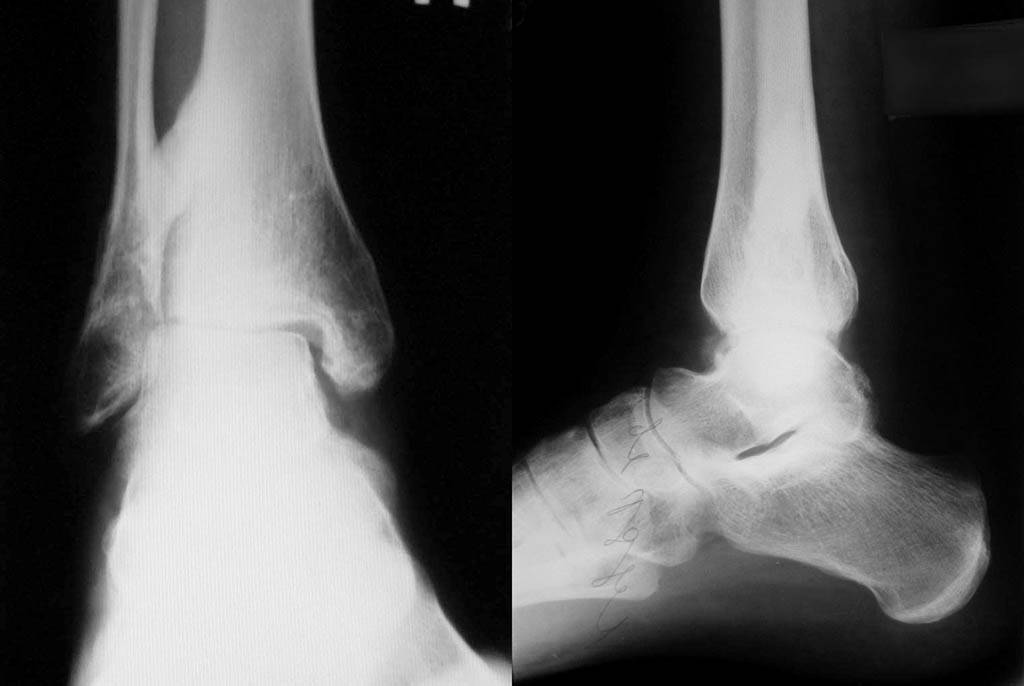

Re: Застарелое повреждение голеностопа

Приложил последние снимки г/стопа.